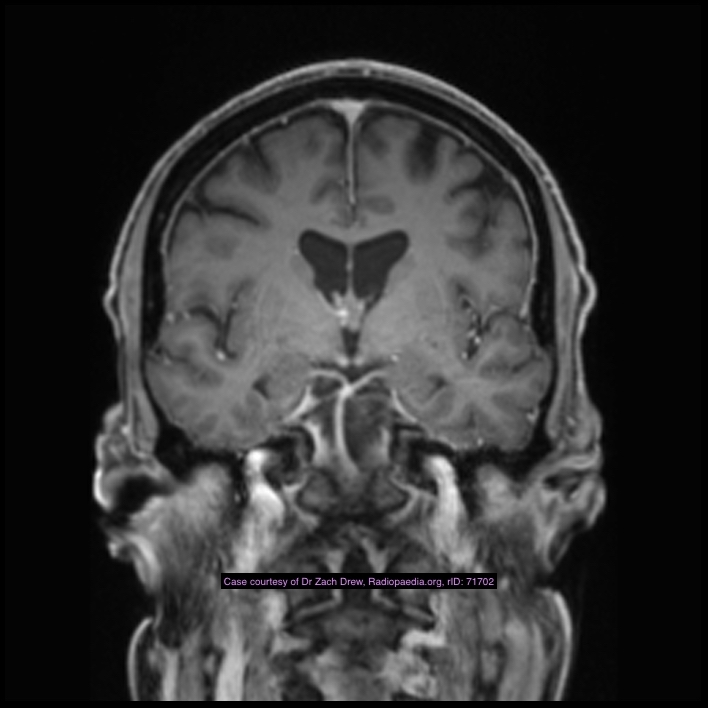

Note the multiple sites of oedema and haemorrhage, involving the brain stem and corpus callosum as well as subcortical white matter and left cerebral peduncle. High FLAIR signal is also seen in the dorsal midbrain. EVD insitu.

Case Discussion

Diffuse axonal injury can be subtle on CT but have devastating consequences for the patient. This is a case of grade III injury (involvement of brainstem) and carries a poor prognosis.

Diffuse axonal injury (DAI), also known as traumatic axonal injury (TAI), is a severe form of traumatic brain injury due to shearing forces. It is a potentially difficult diagnosis to make on imaging alone, especially on CT as the finding can be subtle, however, it has the potential to result in severe neurological impairment.

The diagnosis is best made on MRI where it is characterised by several small regions of susceptibility artifact at the grey-white matter junction, in the corpus callosum, and in more severe cases in the brainstem, surrounded by FLAIR hyperintensity.

Diffuse axonal injury is characterised by multiple focal lesions with a characteristic distribution: typically located at the grey-white matter junction, in the corpus callosum and in more severe cases in the brainstem (see: grading of diffuse axonal injury).

MRI is the modality of choice for assessing suspected diffuse axonal injury even in patients with entirely normal CT of the brain 5,6. MRI, especially SWI or GRE sequences, exquisitely sensitive to paramagnetic blood products may demonstrate small regions of susceptibility artefact at the grey-white matter junction, in the corpus callosum or the brain stem. Some lesions may be entirely non-haemorrhagic (even using high field strength SWI sequences). These will, however, be visible as regions of high FLAIR signal.